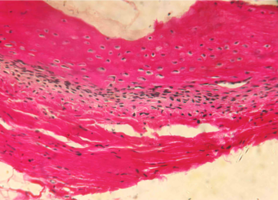

Репаративные процессы на 14 сутки после пластики костного дефекта смесью лиофилизированной аллоспонгиозы и ГАП 1:1.

На обзорной микрофотографии при малом увеличении (х100) видна зона вмешательства, содержащая имплантированный композит, представляющий собой смесь аллогенных спонгиозы и ГАП (рис. 2).

После проведенной предварительной деминерализации костей нижней челюсти в процессе стандартной гистологической проводки кристаллы ГАП в большинстве своем подвергаются растворению, поэтому не видны на препаратах либо видны лишь в единичных случаях.

На их месте чаще всего обнаруживаются округлой либо овальной формы пустоты в костном веществе имплантированной спонгиозы или в прилежащей к зоне пластики соединительной ткани.

Область вмешательства окружена интактной костью нижней челюсти и прилежащими соединительной и мышечной тканями.

Аллогенная спонгиоза в зоне пластики визуализируется в виде безъядерной субстанции костного строения, имеющей губчато-ячеистую структуру.

Содержит множество округлой, овальной и неправильной формы ячеек, заполненных соединительной тканью.

Костный компонент спонгиозы интенсивно окрашивается в ярко-красный (при окраске пикрофуксином по Ван Гизон) или ярко-розовый (при окраске гематоксилином и эозином) цвет.

Рис. 2. Нижняя челюсть кролика через 14 суток после остеопластики слева, смесь лиофилизированной аллоспонгиозы и ГАП 1:1.

Область пластики, заполненная имплантатом аллогенной спонгиозы, обозначена черными стрелками.

Синими стрелками указана интактная кость.

Окраска - пикрофуксин по ван Гизон, х100.